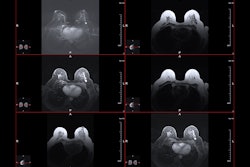

Walter highlighted MRI’s high sensitivity, specificity, negative predictive value, and cost-effectiveness in screening high-risk patients. She and colleagues studied how supplemental MRI adds to total breast cancers found in women with dense breasts after the women received a negative screening mammogram.

The researchers set the time between initial screening mammogram and MRI exams at two months to reduce interval cancers. The women underwent a sub-10-minute MRI protocol, with readers having more than 15 years of experience.

Eight women were recalled due to positive breast MRI findings. This translates to a recall rate of 40 per 1,000 women.

Image-guided biopsy revealed four cancers, three of which were deemed invasive in women presenting with category C breast density. The other one cancer case was a non-calcifying ductal carcinoma in situ (DCIS) in a woman with category D breast density. This resulted in a cancer detection rate of 20 per 1,000, a positive predictive value (PPV) of recall of 50%, and a PPV of biopsy of 62.5%.